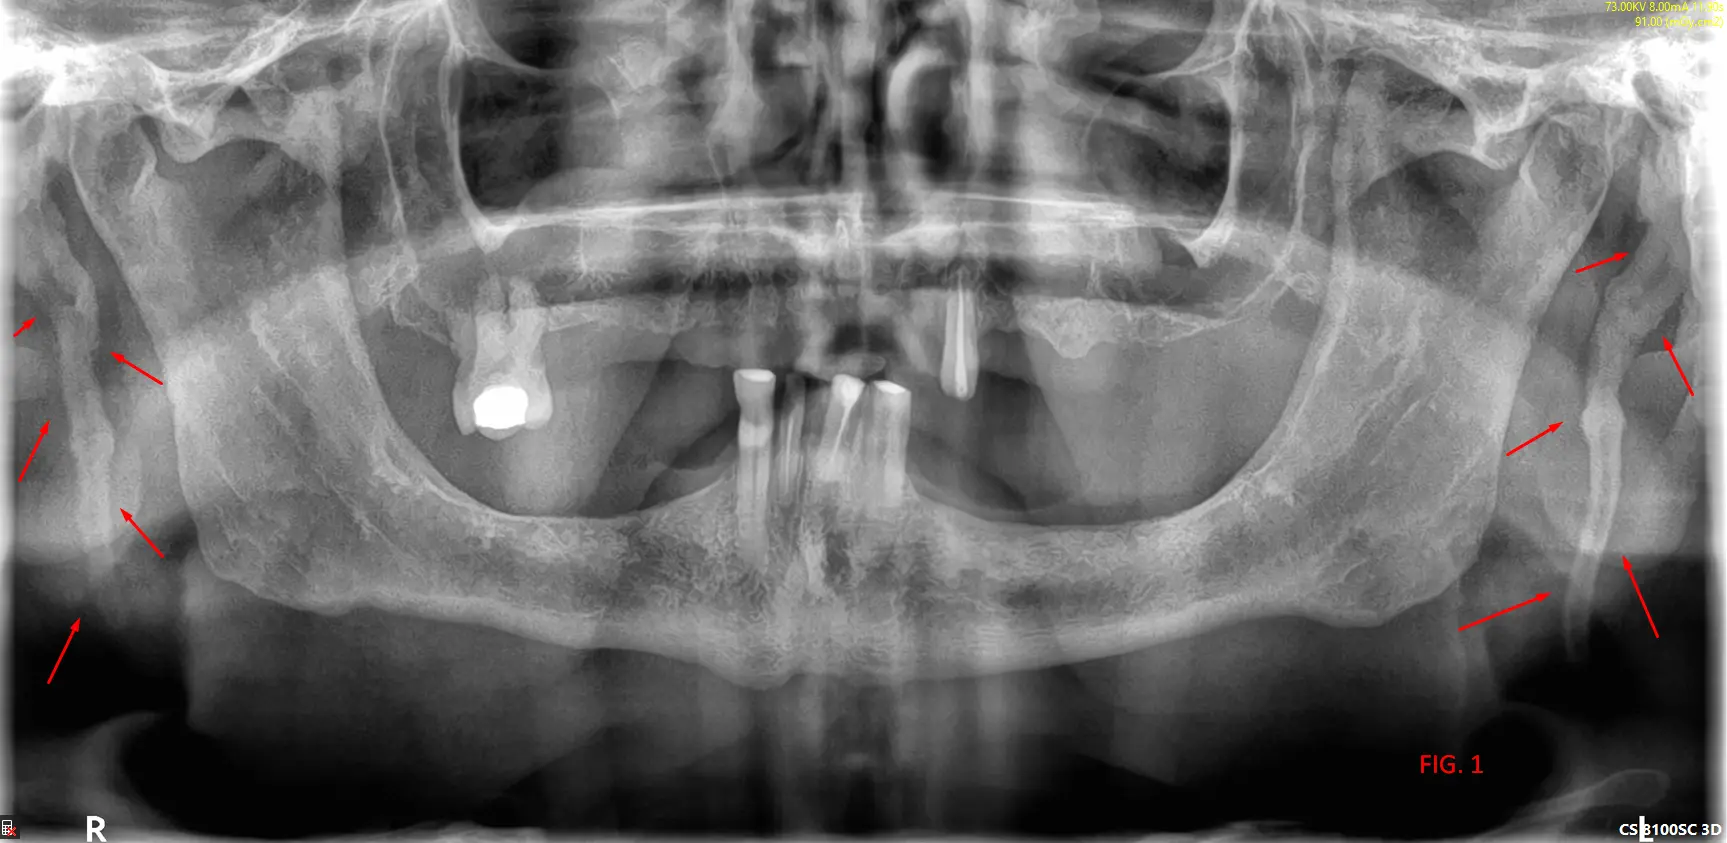

En el análisis de la ortopantomografía, se identifican estructuras radiopacas bilaterales de morfología alargada. Estas formaciones se extienden desde la base del cráneo (apófisis estiloides) con una trayectoria descendente y anterior hacia el hueso hioides (FIG 1, 2 y 3). Basándose en las características imagenológicas, se concluye que se trata de una osificación bilateral del ligamento estilohioideo, un hallazgo que suele presentarse de forma incidental